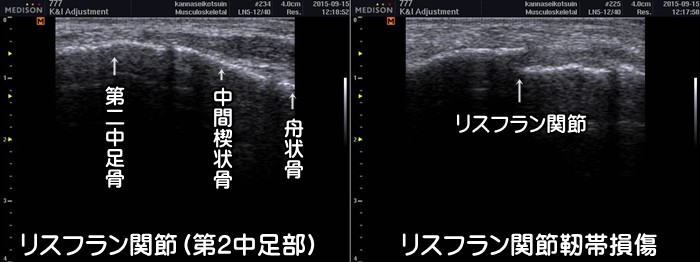

リスフラン関節靭帯損傷

足の甲、特に第2趾に沿って痛みがある場合はリスフラン関節靭帯損傷を疑います。つま先立ちのような状態で体重をかけると痛みが出現します。単なる捻挫と見過ごされやすい少し特殊な靭帯損傷です。